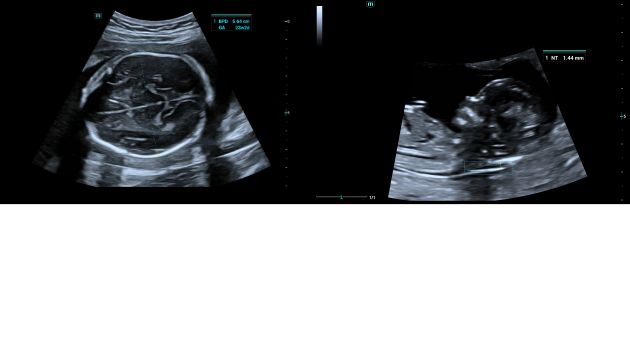

Automatic measurements of the most frequently examined parameters, including BPD, HC, FL, AC, OFD and even NT as early as 11 weeks, are available with a single click for higher productivity and reproducibility.

Consona Series Women Health Solution - Smart OB/NT feature image